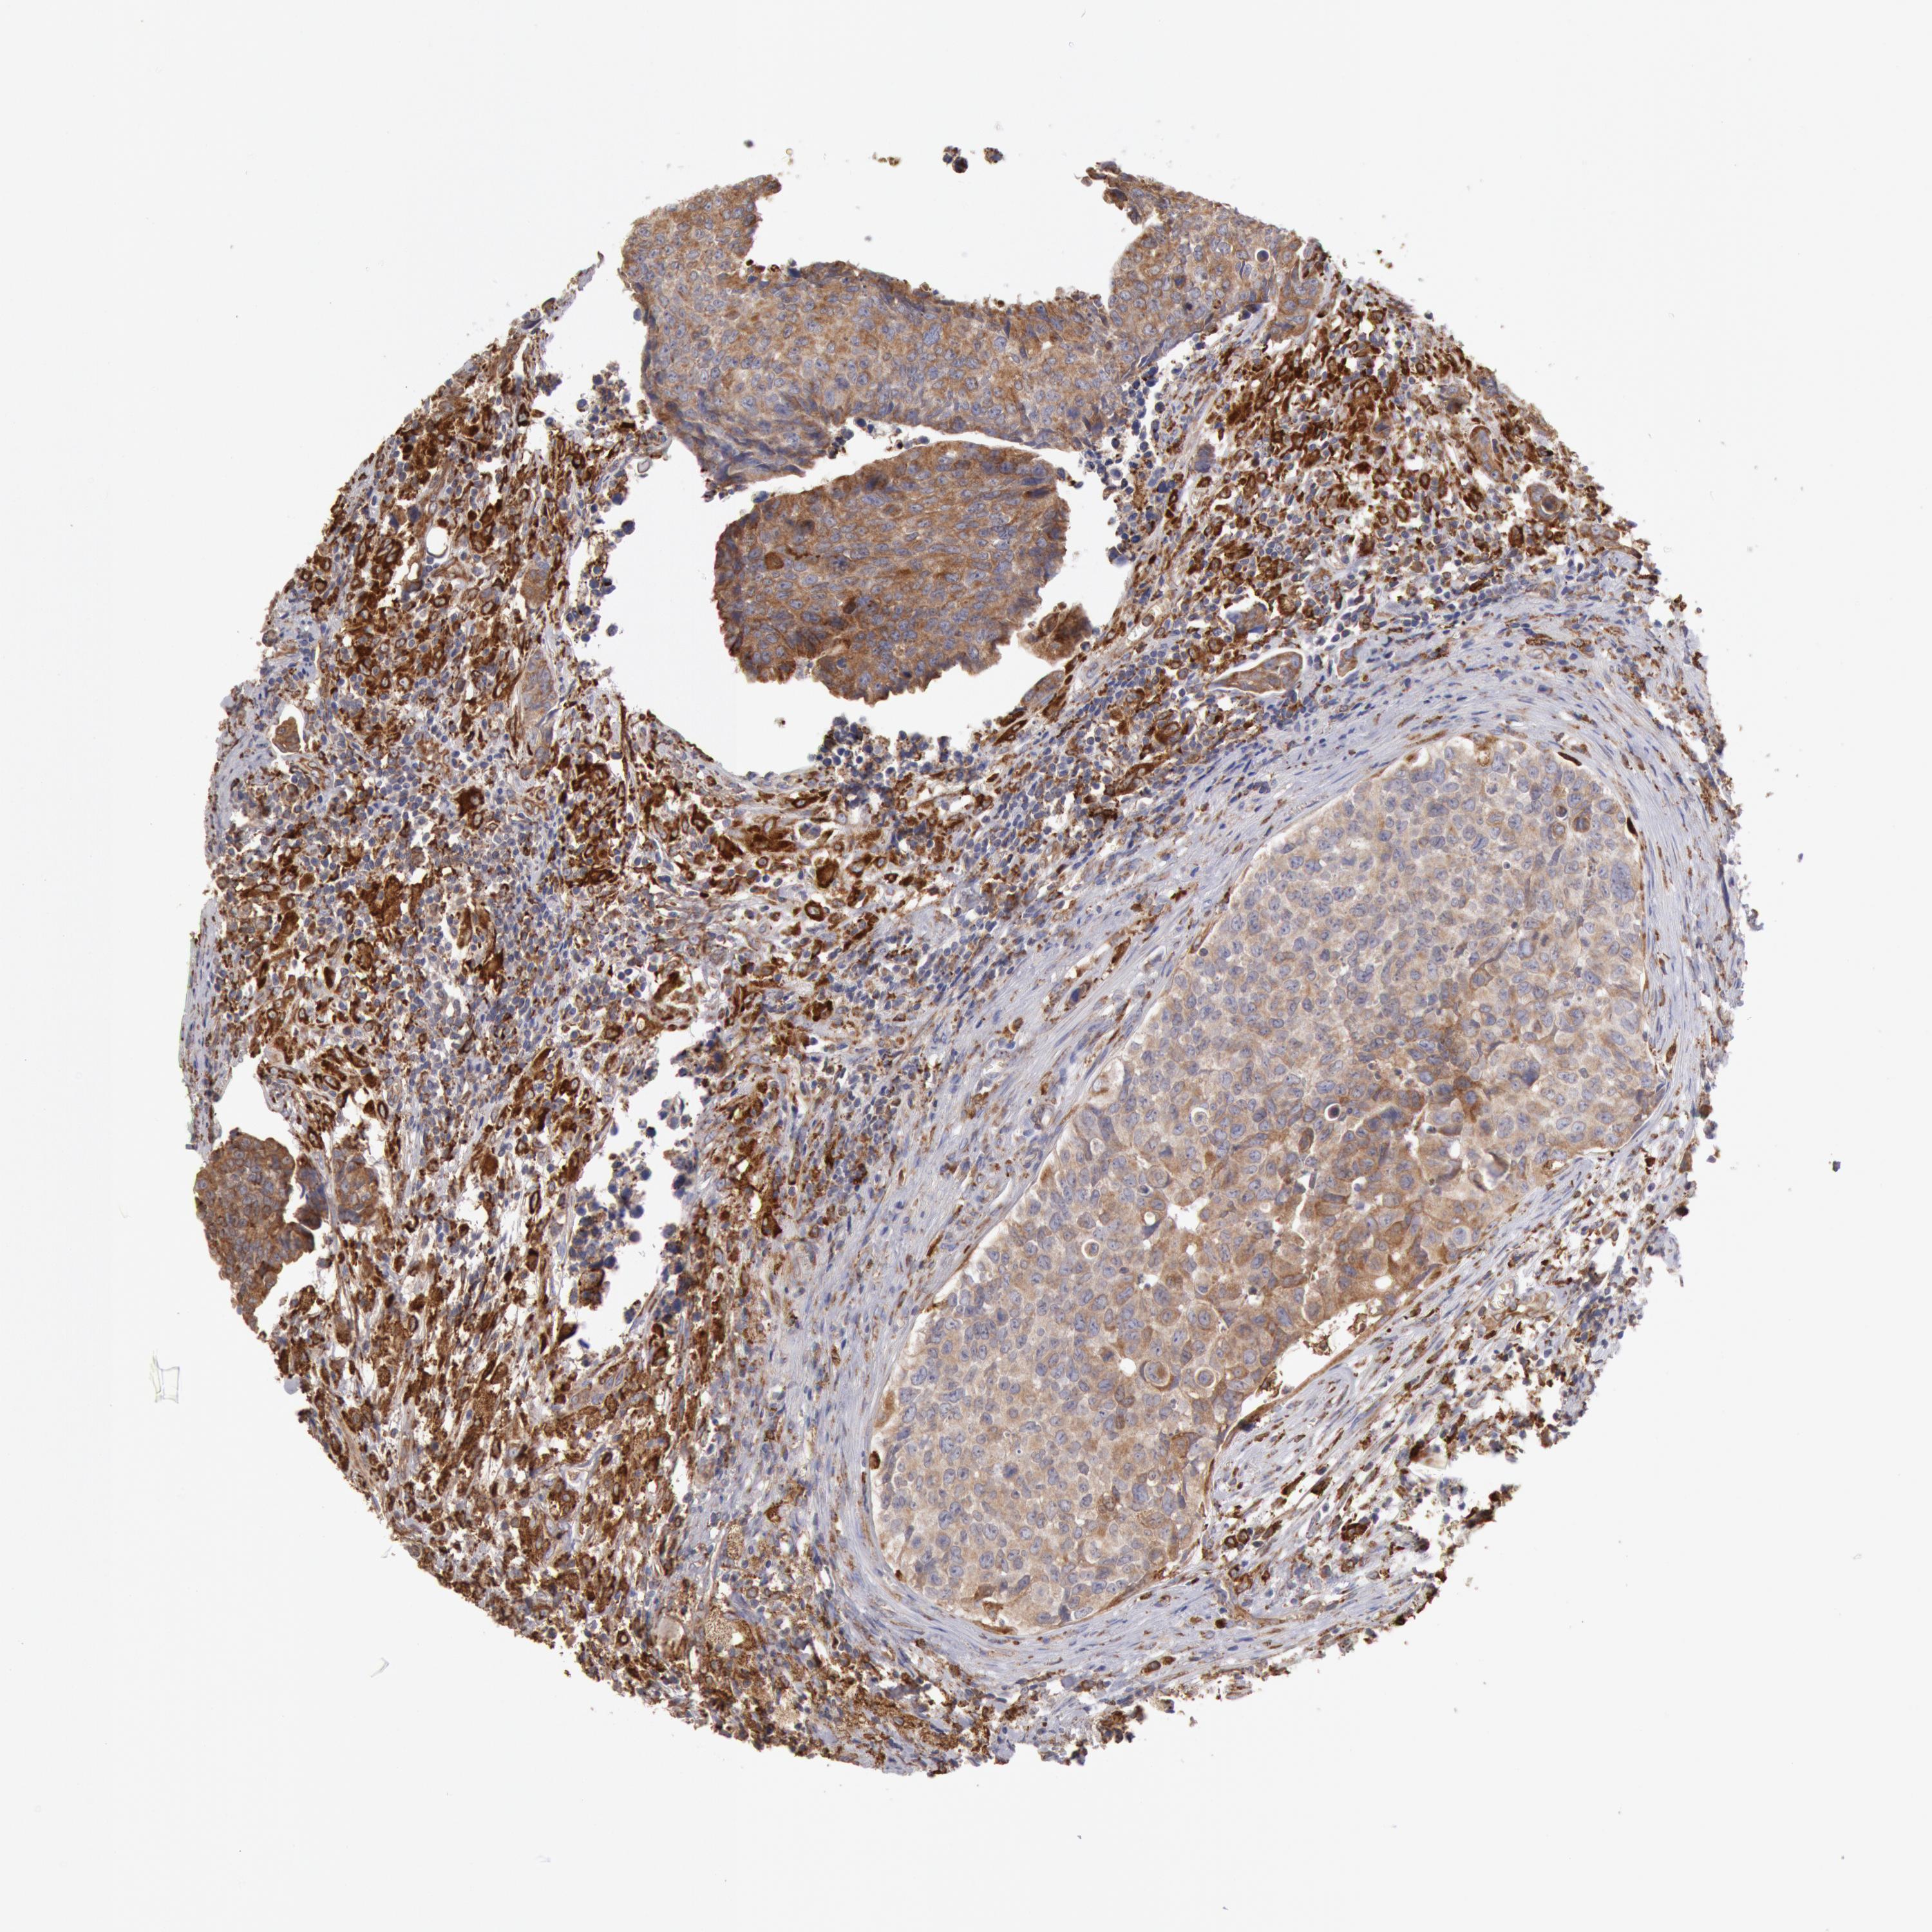

UROTHELIAL CANCER - Protein expressioni

A mouse-over function shows sample information and annotation data. Click on an image to view it in a full screen mode. Samples can be filtered based on level of antibody staining by selecting one or several of the following categories: high, medium, low and not detected. The assay and annotation is described here.

Note that samples used for immunohistochemistry by the Human Protein Atlas do not correspond to samples in the TCGA dataset.

Antibody stainingi

Antibody staining in the annotated cell types in the current human tissue is reported as not detected, low, medium, or high, based on conventional immunohistochemistry profiling in selected tissues. This score is based on the combination of the staining intensity and fraction of stained cells.

Each image is clickable and will lead to virtual microscopy that enables deeper exploration of all samples and also displays staining intensity scores, fraction scores and subcellular localization as well as patient and tissue information for each sample.

Antibody HPA001318

Staining

High

Medium

Low

Not detected

Intensity

Strong

Moderate

Weak

Negative

Quantity

>75%

75%-25%

<25%

None

Location

Nuclear

Cytoplasmic/membranous

Cytoplasmic/membranous,nuclear

Adenocarcinoma, NOS